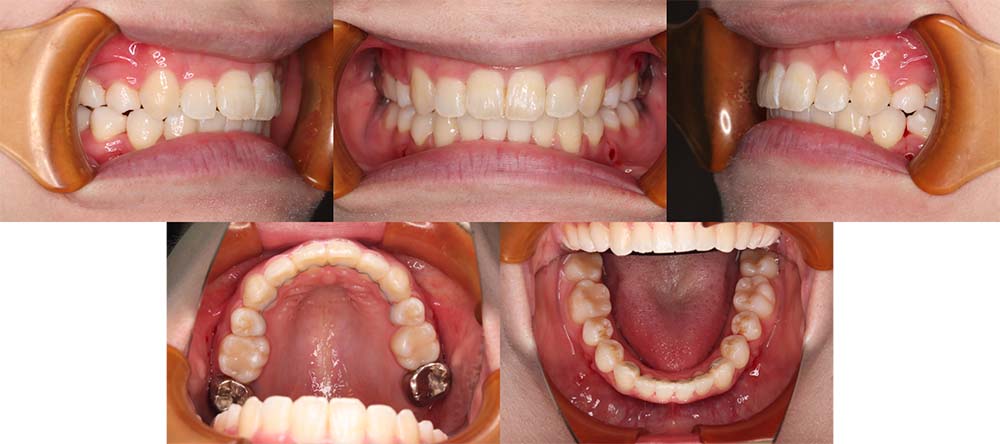

| 症例分類 | 上顎前突、口唇突出 |

| 診断名 | 左下4先天欠損を伴う上下前歯部叢生と骨格性上顎前突 |

| 主訴 | 出っ歯、下の歯がガタガタ、乳歯が1本ある |

| 年齢 | 31歳4ヶ月 |

| 性別 | 女性 |

| 抜歯部位 | 上の左右第一小臼歯と右下第二小臼歯と左下第二乳臼歯(4本) |

| 使用装置 | 上下裏側のワイヤー装置 |

| 治療期間 | 2年9ヶ月 |

| 保定装置 | 固定式保定装置、取り外し式保定装置(8時間) |

| 費用 |

[検査・診断料] ¥49,500 [基本施術料] ¥1,331,000 [調整料] ¥5,500/回 [抜歯] ¥5,500/本 [保定装置] ¥55,000(税込) 抜歯や虫歯治療は他院にて費用が別途かかります。(抜歯¥4,000〜10,000/本)

左下の永久歯が先天欠損で子供の歯が残っていて、その歯が抜けそうになったこともあり、矯正治療を考えて来院されました。

上下叢生と口唇閉鎖不全のため上下の抜歯をして治療をしました。下顎左側乳歯を抜去して治療をしました。

歯の動きが少しゆっくりだったため、予定より治療期間が伸びてしまいましたが問題なく咬合させることができました。